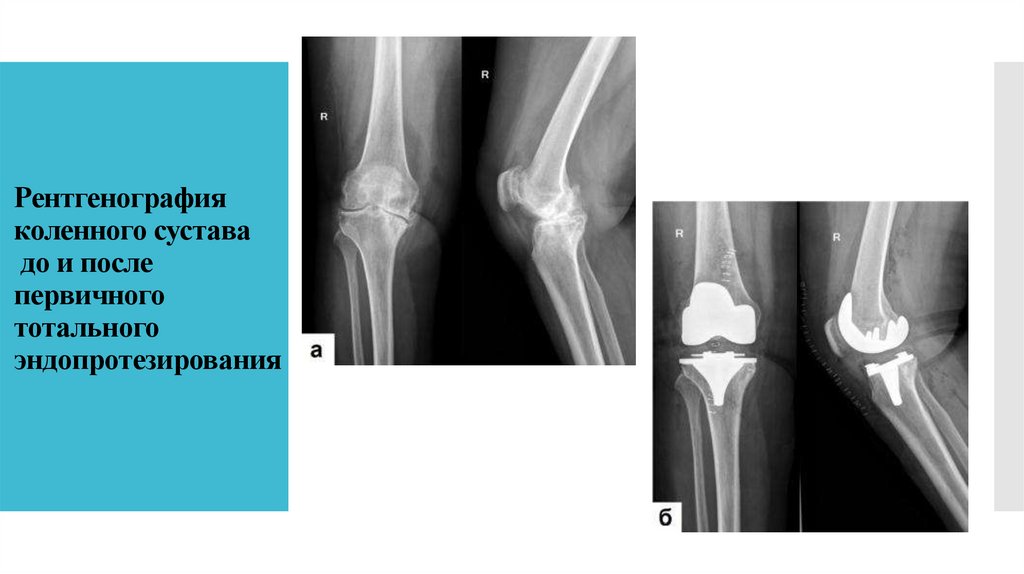

22. Рентгенография коленного сустава до и после первичного тотального эндопротезирования

23. Эндопротезирование крупных суставов